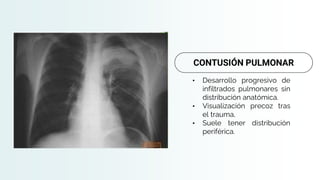

CONTUSIÓN PULMONAR

Hemorragia interstical con colapso y ocupación alveolar con sangre

Condiciona una zona perfundida pero poco ventilada

Diagnostico radiológica

• Desarrollo progresivo de

infiltrados pulmonares sin

distribución anatómica.

• Visualización precoz tras

el trauma,

• Suele tener distribución

periférica.